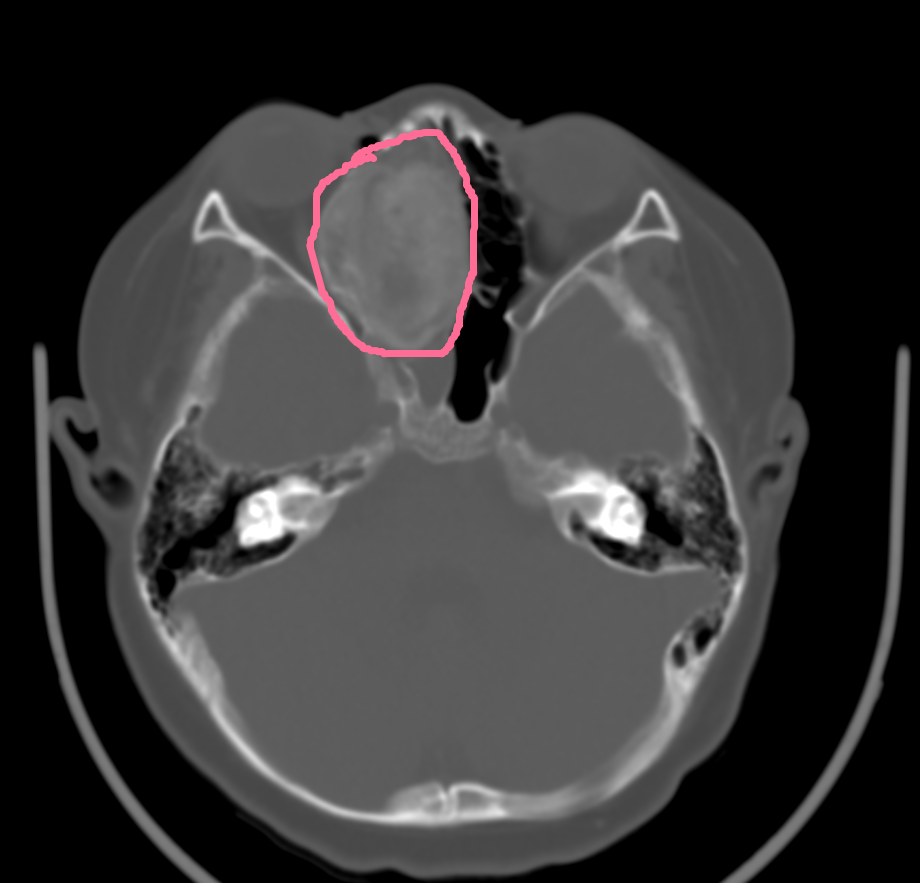

家住长沙雨花区的9岁6月男孩阔阔,在1月前出现鼻塞,流脓涕、口腔内有水泡,家长当时觉得就是个“小感冒”,未引起重视。后来他突然说右侧面部胀痛及头痛,家长才带他到当地社区医院就诊,血常规提示感染指标高,予抗生素抗感染治疗,但症状未见好转,而且头痛越来越厉害,于是家长带其来到湖南省儿童医院,耳鼻咽喉头颈外科医师为其行电子鼻咽喉镜检查发现其右侧鼻腔有一新生物。为了明确肿物来源及与周围组织的关系,予其行MR平扫+增强,结果示右侧鼻腔及筛窦区可见一大小约3.6x4.6x4.8cm类圆形混杂密度肿块影,边界较清晰,肿块部分凸入右侧上颌窦及眶锥内,右侧内直肌及视神经局部受压,鼻中隔局部受压向左侧移位,提示右侧鼻腔及筛窦区占位性病变:骨化性纤维瘤?手术是本病唯一根治的方法,为了保证手术安全及手术精准性,减少术中出血,耳鼻咽喉头颈外科进行了病例讨论,为患儿制定了个性化手术方案,目前阔阔已经顺利通过手术,鼻塞、头痛症状得到了明显改善。